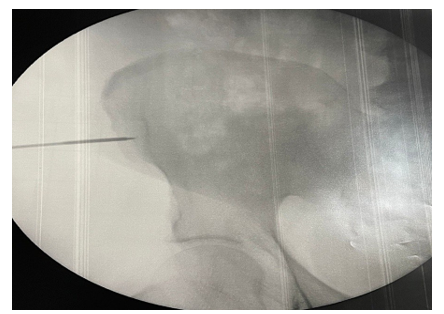

Patients were pre-treated with three intra-articular injections (local anesthetic and triamcinolone 40 mg) on a weekly basis to reduce joint inflammation. In summary, mononuclear cells were harvested from the iliac crest in a sterile operative field and under local anesthesia. Using a trocar inserted into the spongy bone, a bone marrow aspiration of up to 60 ml was performed. Utilizing the Sepax Cell Processing System, mononuclear cells were directly selected in the operating room, eliminating red blood cells and plasma, thus reducing the volume of aspirated material (figure 1

Figure 1: This Image Illustrates the Procedure of Bone Marrow Aspiration from the Iliac Crest. A Trocar is Inserted Into the Spongy Bone to Collect Mononuclear Cells, Which are Essential for the Subsequent Stem Cell Therapy in Joint Regeneration